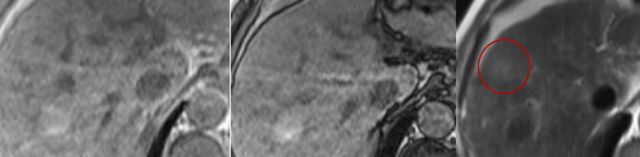

例二:识别肝硬化背景下肝细胞癌(HCC)

HCC发病与乙型、丙型肝炎和肝硬化密切相关,特征较为特殊,是连续性病变,结节样病灶(RN、DN)至癌变过程中可分为多个步骤。

由于 HCC 中多不具备有正常功能的肝细胞,因此,在肝胆特异期,病灶较周围肝实质而言,呈明显低信号,但是经研究报道,少部分 HCC会吸收一定量的对比剂,在肝胆特异期呈等、稍高信号,其证实与HCC 的病理分级有关。